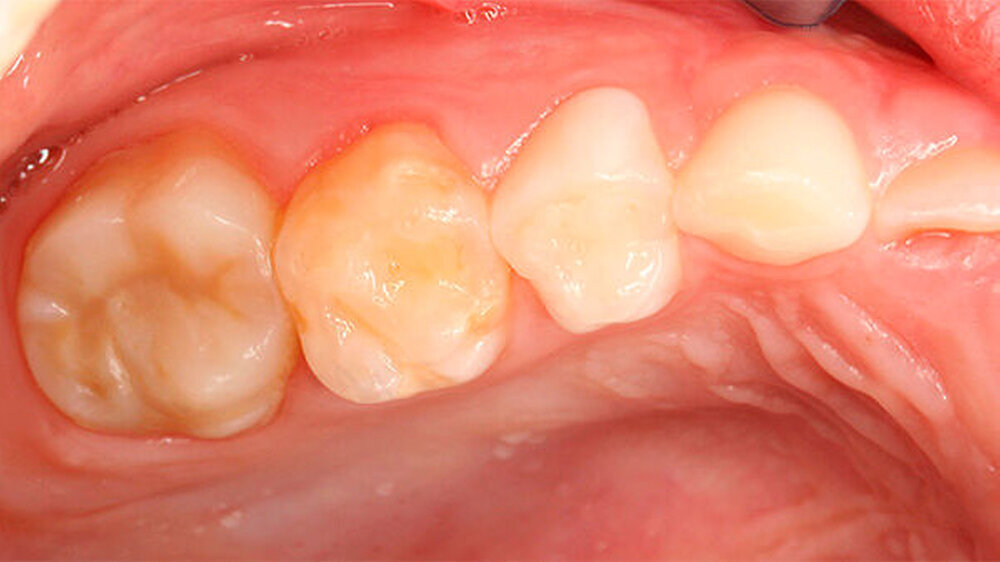

Zusätzlich zu den Frontzähnen waren die Molaren in sehr unterschiedlicher Ausprägung betroffen. Dies reichte von lediglich kleineren Opazitäten bis zu darüber hinausgehenden Schmelzverlusten: Im ersten Quadranten war Zahn 16 klinisch vollkommen unauffällig, hier zeigte aber der zweite Milchmolar insbesondere bukkal Opazitäten und Einbrüche des Schmelzes (Abbildungen 3 und 4) auf.

Zu ergänzen ist, dass die mesio-bukkale Opazität an Zahn 65 zwischen dem Zeitpunkt der Aufnahme der Patientin und der Präparation wenige Wochen später einen Einbruch der Schmelzoberfläche aufwies (Abbildungen 4 bis 6).

Seit einigen Jahren wird - insbesondere in den Niederlanden - auf ein vermehrtes Vorkommen von hypomineralisierten Milchmolaren aufmerksam gemacht. Diese scheinen ein Risiko für eine MIH in der bleibenden Dentition darzustellen [Elfrink MEet al., 2012]. Aber ebenso wie bei der MIH sind auch hier die Ursache sowie der Mechanismus bisher weitestgehend ungeklärt. Im vorliegenden Fall trat beides bei der Patientin auf, zusätzlich war der Zahn 83 von einer Opazität betroffen.